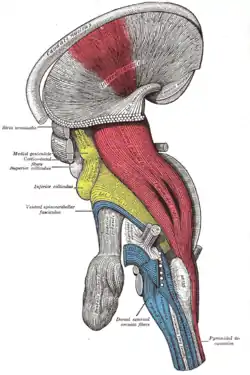

Deep dissection of brain-stem. Lateral view. ("pyramidal tract" visible in red, and "pyramidal decussation" labeled at lower right.) | |

Dissection of brain-stem. Lateral view.

Dissection of brain-stem. Lateral view. Superficial dissection of brain-stem. Ventral view.